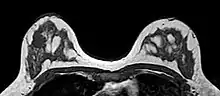

O sistema de relatórios e dados de imagem da mama (BI-RADS, do inglês Breast Imaging Reporting and Data System) é uma sistematização internacional para avaliação mamária, interpretação e laudos de exames de imagem da mama. No início, era utilizado apenas à mamografia, mas também é usado na ultrassonografia e ressonância magnética.[1]